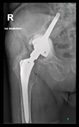

Figure 2.

Design steps of the aiming device: (a) Stemmed acetabular cup with guiding wire; (b) drawing of the guiding sleeve and the reference points; (c) connection of the reference points and the guiding sleeve; and (d) adjustment of the handle.

Next, the aiming device was designed, starting with the guiding sleeve. Its length was typically 60–70 mm, which provides appropriate guidance. However, this length is influenced by the position of the femur, which can be seen in the 3D reconstruction. Even with a diameter of 10–12 mm, the guide wire is safely targeted (Figure 2b). A chamfer of 1–2 mm around the inlet surface of the guide cylinder ensures that no cutting edge is formed at the boundaries of the surfaces. On the outlet side, also chamfered, was left 2–3 mm from the bone surface, thus avoiding the possibility of the guide stem accidentally resting on the surface of the shaft, thus altering the aiming direction. In the early versions, the targeting body adopted the unique shape of the damaged side of the hip, with a groove for the index finger to help hold it in position. In practice, however, it proved difficult to drill and hold the finger in a safe position at the same time. Furthermore, it was found to be problematic when the targeting device was in contact with the bone over a large surface area. The accuracy of the 3D reconstruction and the preparation of the hip may have had a negative effect on the direction of the targeting device in the event of large surface contact and, thus, the accuracy of aiming. These observations led to further development. Later practice was to position the target with three reliable bony sections. Once the support points were designated, slots were constructed between the designated points and the central part of the device. A hexagonal and a triangular socket was constructed to replace the finger positioning. A stainless-steel hand tool was used to retain it in position. However, the hand tool that was used limited the space available for the drilling tool, making it difficult to use the targeting device.

Our previous practice was to use three reliable bony formations to position the aiming device, but experience has shown that these can break off during surgery. However, in addition to two titanium screws, a third point on the lower bony frame provided a secure three-point fixation. For the ideal adjustment of its position, the support arms ending in 12 mm diameter spheres wrapped around the head of the two reference screws, and the third one touched a reliably solid part of the lower edge of the bony acetabulum. The edited spheres, using a Boolean subtraction operation, take the shape of the selected periacetabular bony anatomical point on the anterior margin of the defective acetabulum and the screw heads. Grooves were created in the spheres for the screw heads, considering the need to be able to remove the targeting device after drilling while keeping the guiding wire in position.

These three reference points were linked to each other and to the guide sleeve by means of suitably designed connecting profiles. It was considered that these reference points would be deep and difficult to reach during the operation, so the aiming cylinder of the guiding wire and the spheres around were connected by means of half-toroids of 50–60 mm diameter, considering bypassing the soft tissue (Figure 2c). In the last, fourth version, to replace the hexagonal and triangular sockets, a handle was added to the aiming device outside the skin surface (Figure 2d).